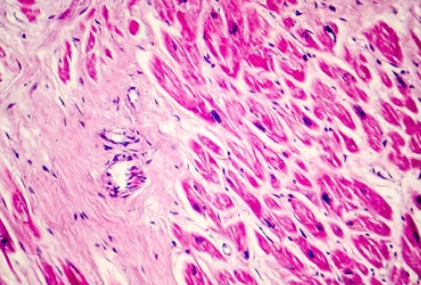

협심증은 관상동맥이 좁아져 발생하는 흉부 통증이라면, 심근경색은 관상동맥이 완전히 막혀 심장근육이 괴사 하면서 발생하는 가슴통증입니다. 따라서 협심증 환자 중 일부는 흉통 없이 호흡곤란만을 호소하기도 한다고 하네요.